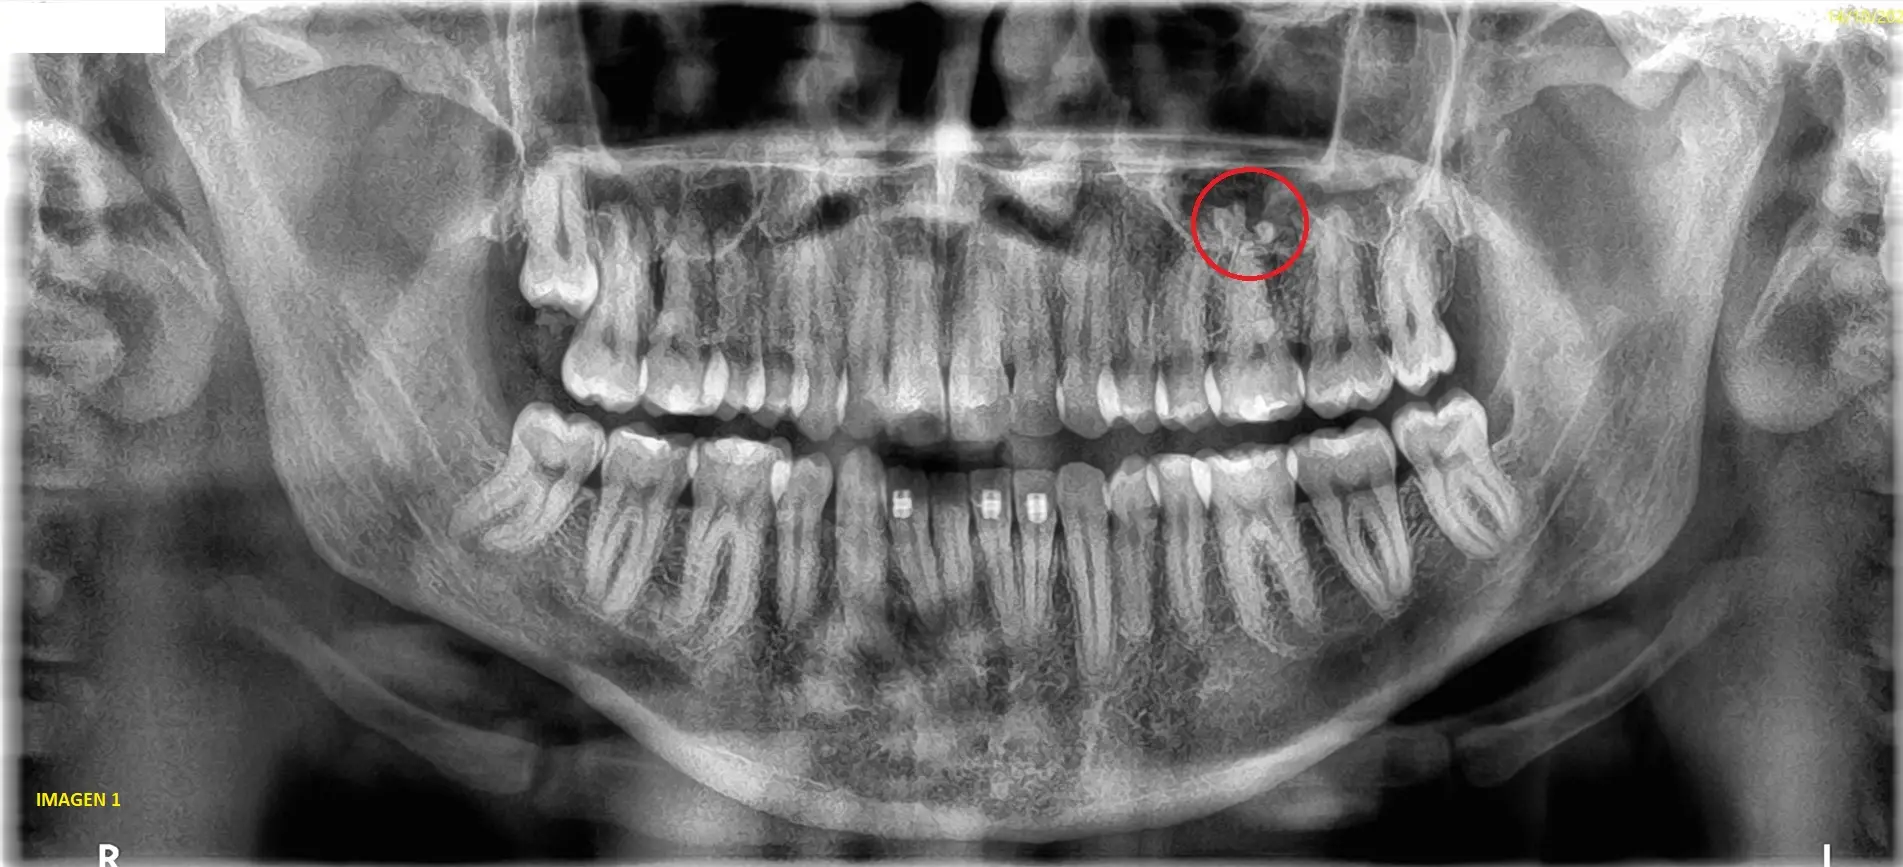

Al efectuar el estudio, pudimos observar imágenes radiopacas anormales en el piso del seno maxilar izquierdo, en cercanías de la raíz de la pieza dentaria 26. (ver imagen 1)

Realizamos una tomografia cone beam sectorizada para un mejor diagnostico.